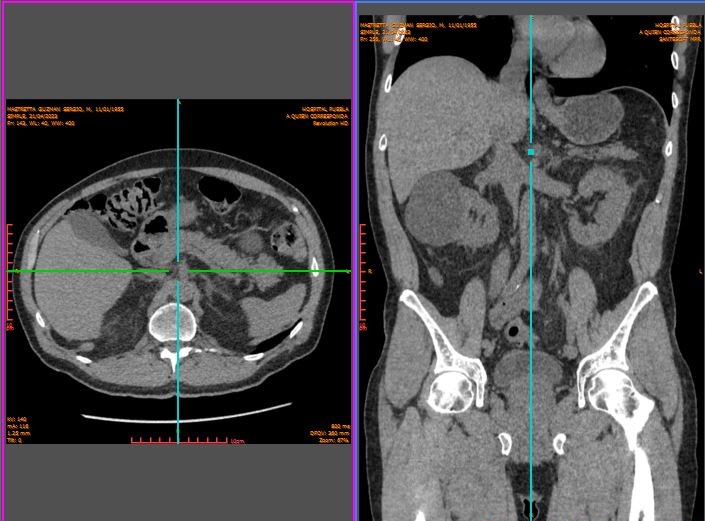

Viernes 21 a las 5.30. Emma me deja en Urgencias y enfila al estacionamiento. Llego encorvado al mostrador y pago con mi tarjeta los cinco mil pesos obligatorios para la recepción de lo que llega de mí. A partir de este momento mi cuerpo es el campo de batalla. Mi atención se centra en el dolor del vientre y las arcadas como luminarias de fuego de artillería. No registro una sola de las preguntas que pronuncia una comedida joven médico de guardia. Alcanzo a escuchar que tiene la encomienda del Médico Tratante, el general Maza Olmos, de realizar la inspección de campo que se identifica como tomografía computarizada, una TAC simple de abdomen. Allá me llevan.

Después, en su despacho en la retaguardia, el Doctor Arturo Arellano Aparicio, radiólogo del Hospital Puebla, escribirá entre otras cosas en su informe:

“Colon con propoestasis generalizada, con presencia de múltiples imágenes seculares en las paredes del segmento sigmoides proximal en relación con divertículos, los cuales predominantemente contienen gas en su interior; se observa engrosamiento parietal y aumento difusos de la atenuación del plano graso pericolónico a este nivel, en una región que abarca una longitud aproximada de 6.5 cms. Sin evidencia de aire y/o líquido libre.”

Ahí, en algún punto de ese sumidero de mi abdomen, la rebelión de las bacterias. (Detalle de TAC tomada el 21 de abril de 2023.)

Ese es un detalle de mí en el juego de la tercera dimensión que produce la tomografía.Vuelto bocaabajo, la panza no pierde su perfil bien ganado a los 69 años.

Pero la libro. La TAC que me realizan el jueves 27 logra esta exclamación del General Maza Olmos:

Mejoría franca. No absceso. Nada Que puncionar

El viernes 28, diez días y 36 mil pesos de Gastos Médicos después –tendré que informarle al SAT–, el General Maza Olmos declara liberada la plaza tras el resultado de la tercera tomografía de mi abdomen averiado.